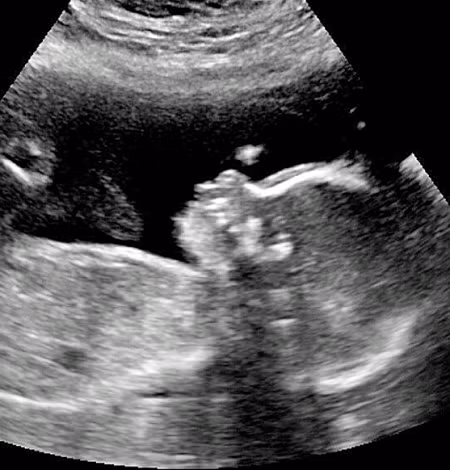

Ngay từ khi còn trong bụng mẹ, các bác sĩ đã siêu âm thấy rõ mái tóc dài của cậu bé, mái tóc khi ấy dài chừng 5 inch (12,7cm).

Cậu được phát hiện có nhiều tóc từ khi trong bụng mẹ.

Angie nói: "Lần đầu tiên chúng tôi nhận ra đứa trẻ có nhiều tóc là khi siêu âm, khi bác sĩ của tôi nói" wow, đứa bé có rất nhiều tóc. " "Nhưng thậm chí tôi đã rất ngạc nhiên khi đứa bé đã có rất nhiều tóc khi mới sinh ra, khi đó tất cả bác sĩ, y tá đều bị sốc bởi vì điều đó”.